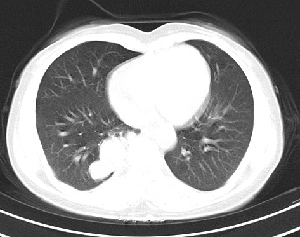

下叶后基底段近膈面见一椭圆形密度均匀增高的阴影,边界较清,其长轴指向内后方,考虑肺隔离症,建议增强扫描了解与主a联系!

右下肺隔离症有可能,另外可能是炎性假瘤

1\\没有什么病史吗,没有看到与腹主动脉有联系呀,肺隔离症不是太象

2\\如果没有明确临床体征,炎性假瘤到是可以考虑

右下肺隔离症考虑,不除外炎性假瘤,建议增强。